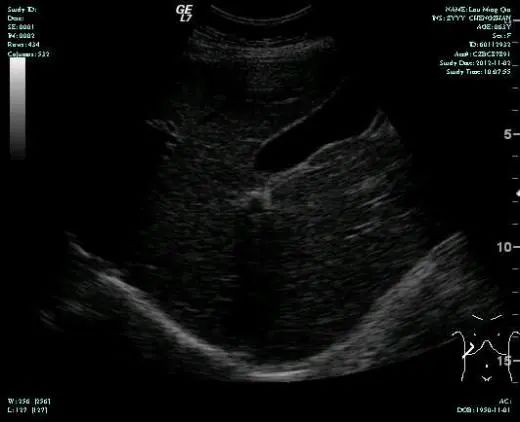

CT-T

CT-H1

MR-H1

影像学检查结果评估:cPD。